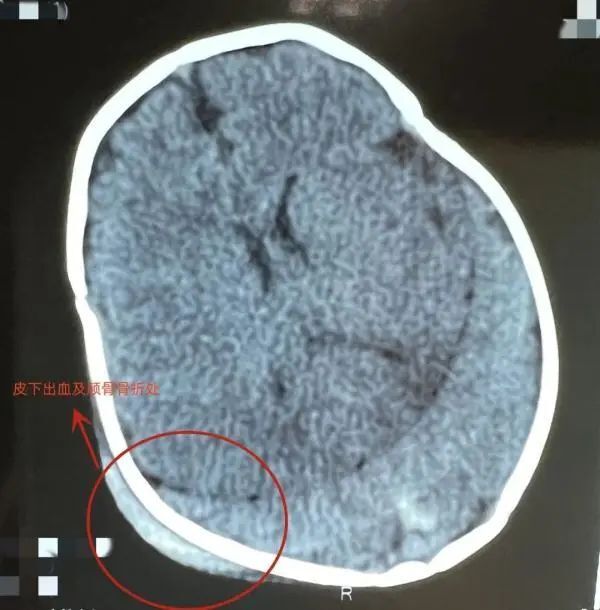

据医院小儿外科主治医师顾春晖介绍,家长抱着孩子坐在副驾驶位,突然急刹车,孩子一头撞在了中控台上,头部肿胀、哭闹不止。

经过头部CT检查,发现皮下有出血,颅骨有凹陷骨折,颅内也有少量出血伴有脑挫伤。经过治疗,孩子病情平稳,出血没有继续增加。